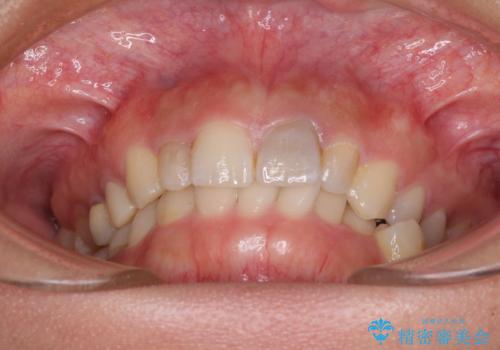

歯列から飛び出た歯 ワイヤー矯正で整った歯列に

- 下顎の歯列から飛び出した小臼歯を気にして来院された患者様です。

歯列以外に、上顎左右側切歯が矮小歯であり、上顎4前歯は失活していたため、矯正治療で歯列を整えるとともに上顎前歯の幅を調整し、矯正治療後にオールセラミッククラウンにて審美歯科治療を行うこととしました。

矯正治療は、小臼歯1本分を歯列に納めないいけない状態であったため、表側のワイヤー装置にて行うこととしました。